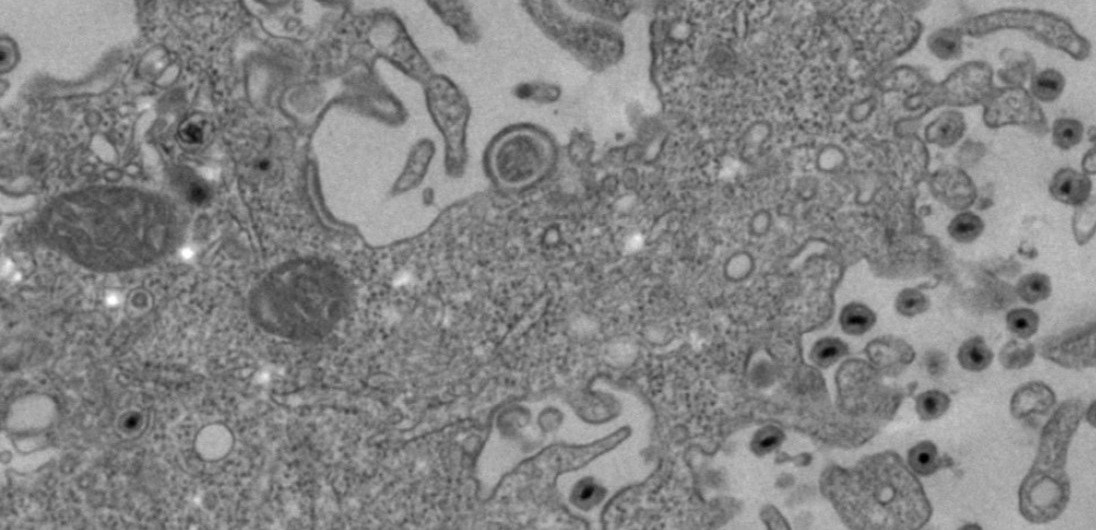

ヒトヘルペスウイルス6(human herpesvirus 6; HHV-6)は1986年に見つかった比較的新しいヘルペスウイルスです。

ウイルスの特徴より現在は、HHV-6AとHHV-6Bに分類されています。HHV-6Bは、乳幼児期に感染して突発性発疹を引き起こし、その後は生涯にわたってヒトの体内に

潜伏感染し続けます。年間、約150例のHHV-6Bの初感染後による脳炎脳症が報告されています。ほぼ100%の成人の体内にHHV-6Bは、潜伏感染していますが、免疫抑制にある移植患者では高頻度にHHV-6Bが再活性化し脳炎や肺炎を引き起こします。薬剤過敏症症候群や多発性硬化症との関連が疑われたりと、臨床上の重要度は高いと考えられます。またHHV-6は、ウ

イルスゲノムの宿主ゲノムへのインテグレートが報告されている、大変ユニークなウイルスです。しかし、潜伏感染、インテグレーション、再活性化のメカニズム、および病態発現機構については、未だ明らかとなっていません。そして、HHV-6は、活性化したT細胞などの免疫系の細胞に感染するという非常にユニークなウイルスです。